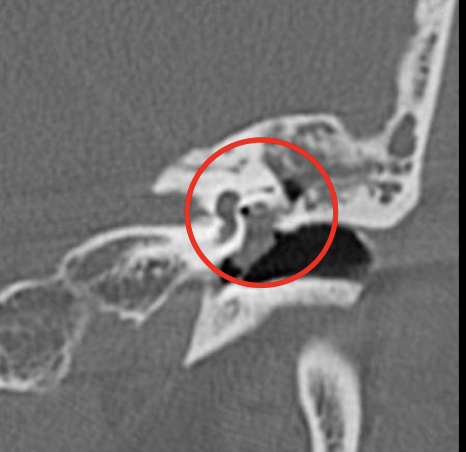

4

A

Otitis media